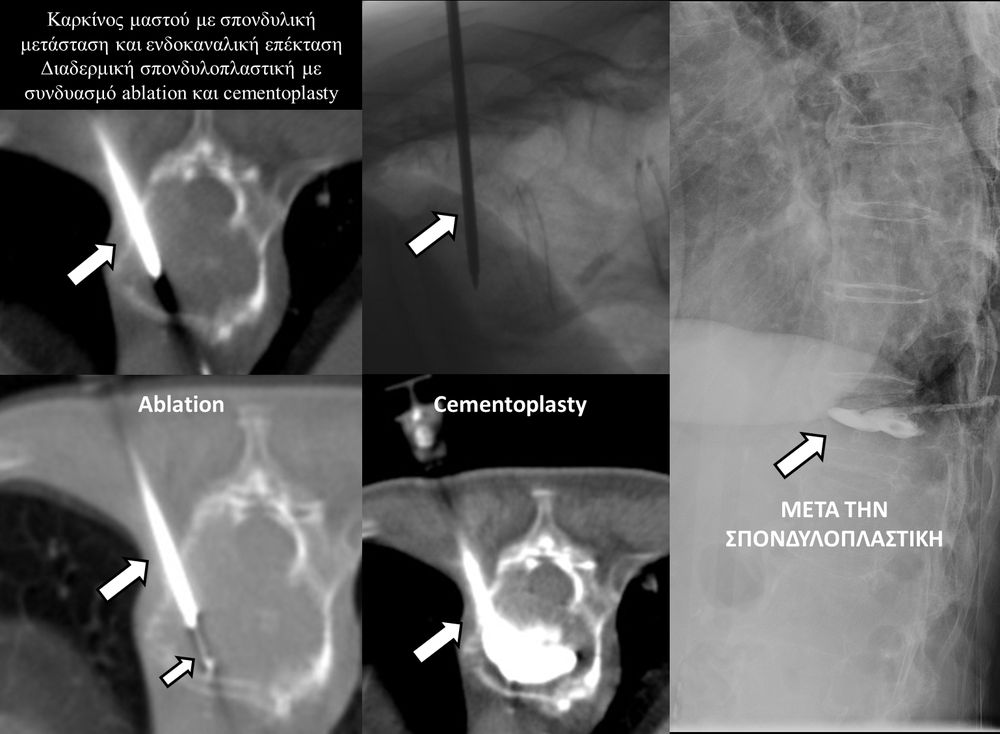

Η τεχνική της διαδερμικής σπονδυλοπλαστικής αφορά την απεικονιστικά καθοδηγούμενη, διαδερμική τοποθέτηση βελόνας εντός του σπονδυλικού σώματος και την υπό συνεχή ακτινοσκοπικό έλεγχο ενδοσπονδυλική έγχυση ακτινοσκιερού, πολυμερούς τσιμέντου (cementoplasty). Oι ενδείξεις της μεθόδου περιλαμβάνουν οστεοπορωτικά και τραυματικά κατάγματα, σπονδυλικές μεταστάσεις, πολλαπλούν μυέλωμα και λέμφωμα.

Ο στόχος της τεχνικής είναι η μείωση του άλγους και η σταθεροποίηση της σπονδυλικής στήλης και επιτυγχάνεται αφ’ ενός με την σταθεροποίηση του σπονδυλικού σώματος και αφ’ ετέρου, επί ογκολογικού υποστρώματος, με την εξώθερμη αντίδραση του πολυμερούς τσιμέντου, η οποία προκαλεί την τοπική καταστροφή του όγκου. Η μέθοδος συνδυάζεται άριστα με την χημειοθεραπεία και την ακτινοθεραπεία και δρα συνεργικά με αυτές.